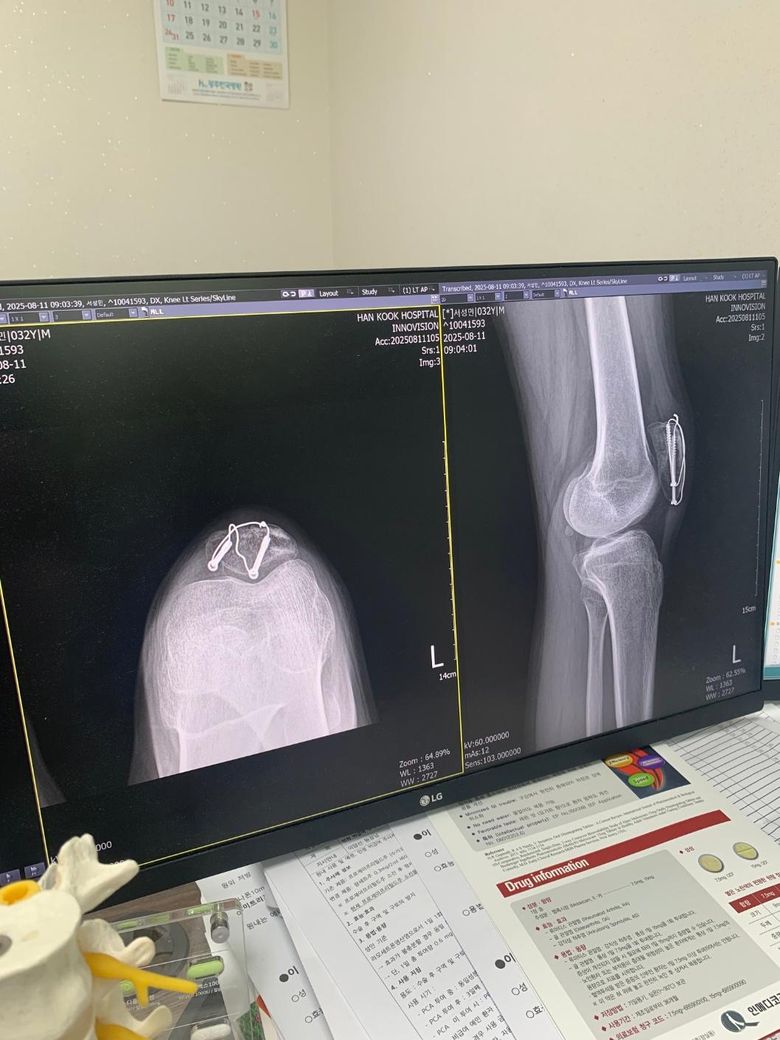

슬개골골절 수술후 8주차 엑스레이입니다 질문좀드릴게여ㅠㅠ

1. 엑스레이상 유합이 잘되고있는건가요?

2. 수술부위를만져보면 한쪽부분이 골절선처럼 움푹파여서 보여지는데 혹시 뼈가 생기다가 만걸까요?

• 1번 째 사진

현재로썬 엑스레이상 유합이 잘되고있는것으로 보여지지만 다방면으로 확인이 필요한 부분이기에 전문의에 소견을 들어보시길 바랍니다.

보통 수술 후 봉합 부위에선 연부조직의 변화로 울퉁불퉁한 느낌이 들 수 있으며, 뼈가 생기다만것은 아니니 걱정하지않으셔도 됩니다.

1. 사진상으로는 수술 이후 금속고정물이 자리를 잡고 골 유합이 이루어지고 있는 것으로 보이는데요, 통증이나 불편감이 심하지 않고 특별히 다른 소견이 없으셨다면 회복이 잘 진행되고 있는 것으로 생각됩니다.

2. 표면의 변화는 뼈의 회복과정에서 일어날 수 있는 표면 변화로 생각됩니다.